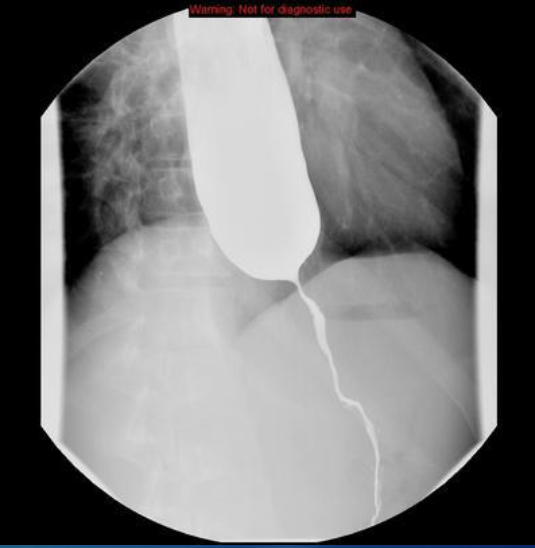

how does fluoroscopy work?

continuous/pulsed x-ray beam passed through body to create real-time, moving images on a monitor

what is an angiogram?

type of vascular interventional radiography

dye that is visible by an x-ray machine is injected into blood vessels of the heart

x-ray rapidly takes a series of images (angiogram)